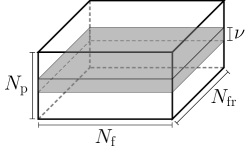

MRI data ( denotes the set of all complex-valued numbers) are observed in k-space (frequency domain), which spans an area of size (cf. Figs. 1a and 1b), with standing for the number of phase-encoding lines and for the number of frequency-encoding ones [1]. Data can be considered as the two-dimensional (discrete) Fourier transform of the image-domain data , i.e., [1]. Without any loss of generality, this study assumes that the “low-frequency” part of is located around the center of the area. Availability of the data over the whole k-space is infeasible in practice; k-space is usually severely under-sampled [3]. There exist several strategies to sample the k-space; examples are the 1-D Cartesian (Fig. 1a) and the radial (Fig. 1b) ones, where the “white” lines in Figs. 1a and 1b denote the available/sampled data, while data in the “black” areas are not observed. A general trend among sampling strategies is to put more emphasis on low-frequency components, which carry contrast information and with high SNR, and select few high-frequency components, which comprise high-resolution image details. The 1-D Cartesian sampling pattern emulates the acquisition of k-space pixels via the 1-D Gaussian distribution, acquiring a large number of samples in the central k-space area while sampling few ones from the “high-frequency” area (cf. Fig. 1a). The radial-sampling pattern consists of radial spokes which yield dense sampling at the center of k-space, while the sampling density is decreased as the spokes move away from the center (cf. Fig. 1b).

In dMRI, an additional dimension is added to the MRI k-space to accommodate time (the axis vertical on the paper in Fig. 1c), resulting in the augmented (k,t)-space. The dMRI (k,t)-space can be viewed, in other words, as the -fold Cartesian product of the -sized MRI k-space, where represents the number of observed MRI frames over time. In dMRI, k-space and image-domain data are connected via , . The (k,t) space is usually highly under-sampled. To extract reliable information from the (k,t)-space data, this work follows [22, 18, 34] and considers a small number () of phase-encoding lines, coined "navigator (pilot) data" (the gray-colored area in Fig. 1c), to learn the intrinsic low-dimensional structure of the data.

To facilitate processing, the (k,t)-space data are vectorized. More specifically, stacks one column of below the other to yield the complex-valued vector where denotes the number of pixels in every frame. To avoid notation clutter, still denotes the two-dimensional (discrete) Fourier transform even when applied to vectorized versions of image frames: . All vectorized k-space frames are gathered in the matrix so that the vectorized image-domain data are , where denotes the inverse two-dimensional (discrete) Fourier transform. The navigator data of the th k-space frame (cf. Fig. 1c), , are gathered into a vector . All navigator data comprise the matrix .